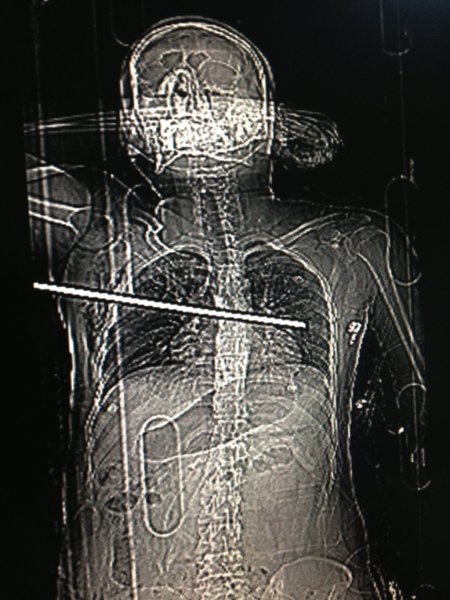

Sultanbeyli’de, çalıştığı inşaatın üçüncü katından düşen işçinin göğsünü inşaat demiri delip geçti. Göğsündeki 35 santimetrelik demirle hastaneye kaldırılan işçinin hayati tehlikesinin bulunmadığı belirtildi.

İnşaatın elektrik işlerinde çalışan 28 yaşındaki Serkan Kara, dengesini kaybedince üçüncü kattan kolon demirlerinin üzerine düştü. Demirlerden biri Kara’nın sağ kol altından girerek sol göğsüne kadar ilerledi. Kara olay yerine gelen itfaiye ekiplerinin çalışmaları sonucu düştüğü yerden çıkartılarak göğsündeki 35 santimetre uzunluğundaki demir ile Dr. Lütfi Kırdar Kartal Eğitim ve Araştırma Hastanesi’ne kaldırıldı.

Hastanede yapılan incelemelerde Kara’nın göğsündeki demirin sol kol altına kadar ilerlediği görülünce hemen ameliyata alındı. Sol akciğeri parçalayan ve kalp zarına zarar verdiği belirlenen inşaat demiri, cerrahların göğüs kafesinin her iki tarafında gerçekleştirdikleri eş zamanlı ameliyatın ardından çıkartıldı.

Kara’nın yanında basın mensuplarına konuyla ilgili bilgi veren Dr. Lütfi Kırdar Kartal Eğitim ve Araştırma Hastanesi Başhekimi Doç. Dr. Recep Demirhan akşam saatlerinde hastanın göğsünde inşaat demiri saplanmış olarak hastaneye getirildiğini söyledi. Demirhan şöyle konuştu: “Hastanın röntgenleri çekildi ve 35 santimetre uzunluğundaki demirin sağ göğüs altından girdiği, sağ ve sol akciğeri parçalayarak ilerlediği, kalp zarına hasar verdiği tespit edildi.” Eş zamanlı olarak sol ve sağ göğüsten yapılan çift taraflı ameliyat ile hastaya müdahale edildiğini, önce kalp zarının ardından iki akciğerin başarılı bir ameliyatla onarıldığını söyleyen Demirhan, saplanan demirin kalbe 3 milimetre daha yakından geçmesi durumunda Kara’nın yaşamasının mümkün olmayabileceğini sözlerine ekledi.